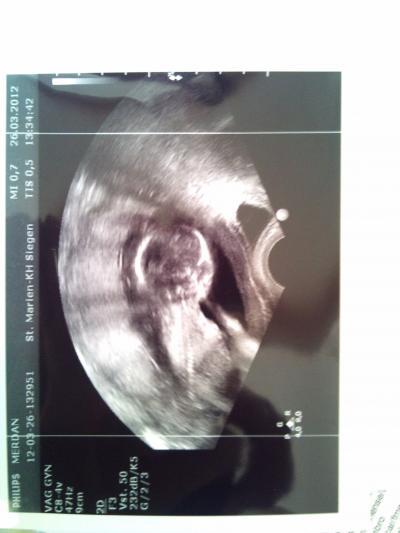

Ohne Outing ist mir gerade sowas von egal!!! Ich habe endlich gesehen, wie sein/ihr Herz schlägt, und wie es (ich glaube) am Daumen nuckelt, oder zumindest die Hand vor dem Gesicht hält... Ich habe auch die kleinen Füßlein gesehen und sogar die Fingerchen konnte man zählen... Ich habe niemanden dabei gehabt, fast beim Baby-TV geweint, aber auf der Heimfahrt konnte ich die Tränen nicht mehr stoppen... Es ist so wunderbar!!! Und der Arzt hat mir gesagt, dass sich alles "nach Plan" entwickelt, und ich einen ganz gesunden Krümel habe... Ich bin so überglücklich! Ich kann's nicht glauben! Wenigstens weiß ich jetzt, dass es keine Phantomschwangerschaft ist :)

also er hat sich ganz viel Zeit genommen. Mir einzeln alles gezeigt (Hände, Füße, Knie, Wirbelsäule, Herz, Kopf, Bauch) also alles auch erklärt (vielleicht ja, weil ich bar bezahlt habe ) und wollte mir am Ende nur ein Bild geben, ich habe aber nach drei gefragt, weil mein Freund auch eins wollte und eins für seine Tochter. Naja, die anderen beiden Bilder sind nicht so gut, wie dieses hier, aber dieses hier gebe ich nicht her :))))) Ich habe mich sehr wohl gefühlt und war erst mal überrascht, als er mir das V-Ultraschallgerät gezeigt hat... Oops dachte ich mir, hättest dich mal besser rasiert *sorry*... Bin da überglücklich raus gekommen und direkt meinem Freund das Bild geschickt... Jetzt ists auch mein Facebook Profilbild lol, also wenn ihr mich finden wollt, sucht nach meinem Krümel ahahahah OOOOOOHHHH jetzt kann ich endlich raus und die Sonne genießen, mit ner Kiste Bier!! Natürlich mache ich Spaß, erstens hasse ich Bier, und zweitens, nichts ungesundes konsumiert, seit dem SS-Test, was ja zur super-Entwicklung meines Krümels wohl viel beigetragen hat!!! Vielen Dank, dass ihr alle mich bei "ups" und "downs" unterstützt habt und mir die Daumen gedrückt habt. Ich liebe dieses Forum :)))))))))))))))